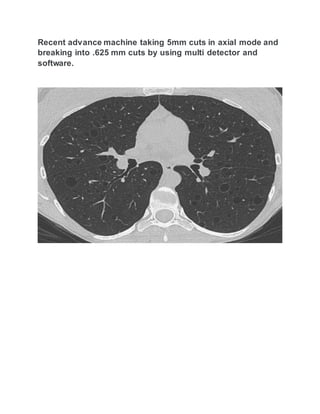

Recent advance machine taking 5mm cuts in axial mode and

breaking into .625 mm cuts by using multi detector and

software.